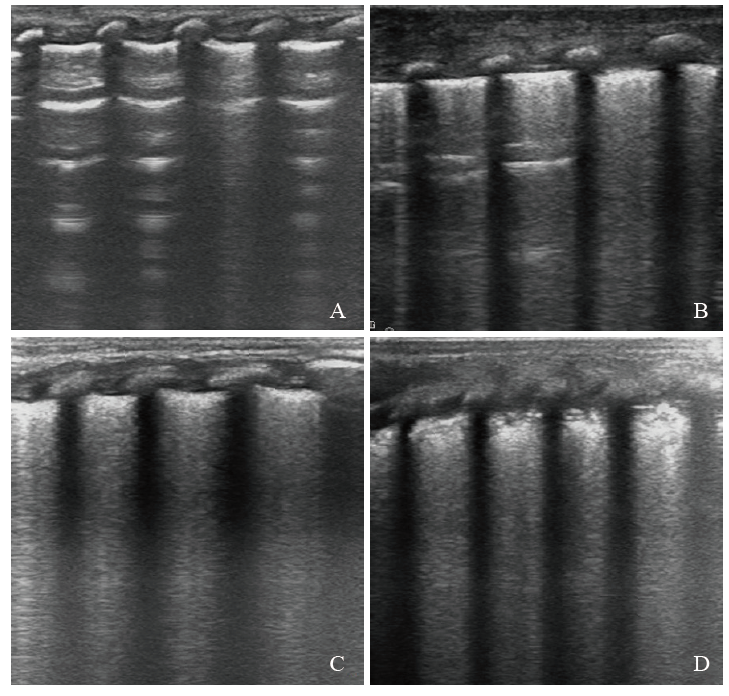

由经过专业LUS培训的新生儿科医师在患儿床边对其进行LUS检查,具体方法如下:分别采取仰卧位、侧卧位或俯卧位姿势,以腋前线、腋后线为界,将肺脏分为前、侧、后3个区域,即双侧肺部共被分为6个区域,同时以双侧乳头连线为界,把双侧肺部再分为上下两个部分,即双侧肺部共被分为12个区域[6,15]。对肺部每个区域进行扫查,对异常LUS声像图进行保存、记录。根据扫描结果对肺部每个分区进行评分,见图1。LUS总评分为12个区域的评分总和,共36分,评分越高,表示通气面积越少,提示肺部病变越严重。

图1 LUS评分示意图

注:A为正常肺组织,LUS评分为0分;B为多肋间的稀疏B线,LUS评分为1分;C为“白肺”,LUS评分为2分;D为肺实变伴支气管充气征,LUS评分为3分。

Figure 1 Diagram of LUS scoring